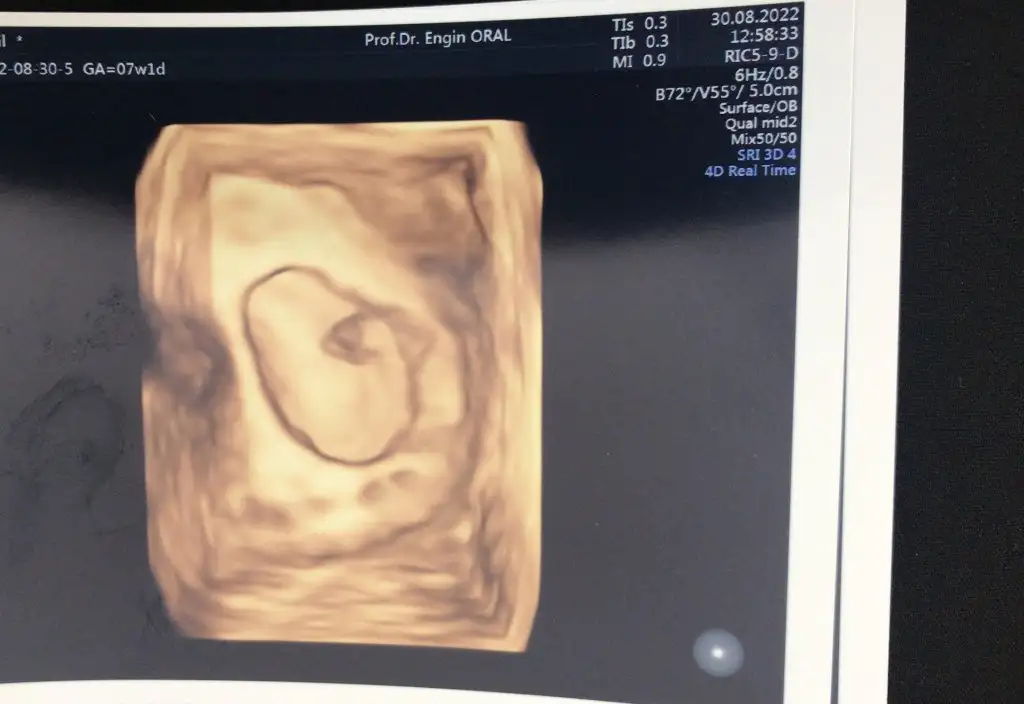

Biz daha önceki transferde beraber sonuç bekliyorduk sanki değil miKızlar keseyi gördükten sonra kalp atışına kadar zaman nasıl geçicek ya. Sanki her sabah bi bilinmezin içine uyanıyoruz. Çok şükür orada olduğunu biliyoruz ama yine de insan endişe içinde bekliyor çok zor değil mi

Amin inşallah çok teşekkür ederim. beta bir gün aralıklarla 3 kere test yaptırdım en son 17 Ağustos baktırdım 3273 çıkmıştı. Doktorum daha yaptırmamı istemedi bugünde ilk muayene de şükür kalp atışı duyulduHayırlı olsun Rabbim sağlıkla kucağınıza almayı nasip etsin beta hcg kacta kalp atışı duyuldu baktimi doktorunuz

Maasallah canm darısı başımızaEvet kızlarrrr bugün ilk muayenemize gittik şükürler olsun kalp atışını da duydum isteyen herkese nasip olsunEki Görüntüle 3121642